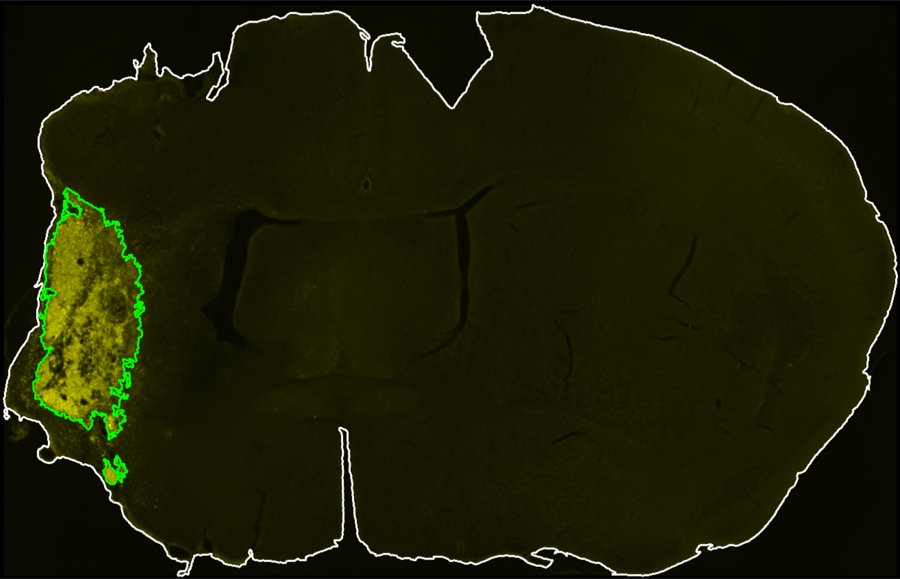

Segmentation Workflow

Interactive controls define midline placement, brain contour thresholds, CD68 thresholds, and exclusion-channel thresholds for section-level infarct segmentation.